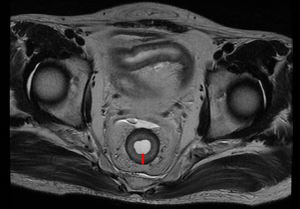

Measurement of rectal wall thickness

Pelvic MRI was used to measure the thickness of the rectal wall without tumor (Figure 2). All of the recruited patients received an initial MRI scan before treatment for tumor staging and a second MRI scan after completion of neoadjuvant chemoradiotherapy. The MRI protocols and measurement have been reported previously (19). The data on rectal wall thickness was collected from the RP database for analysis.

The maximum diameter of the rectal wall thickness of the two groups, not including the location of the tumor, was measured on the T2 axial image of the pelvic MRI before and after radiotherapy (Table 3). After radiotherapy, the thickness of the rectal wall was markedly increased in the RP group. The relative change of rectal wall thickness (ΔL%) was more observable in the RP group than in the nRP group (P<0.01).

Manifestations in typical images of RP can include the thickening of the rectal wall and the obvious thickening of the mucosa and/or serosal layer, which present a stratified change or “target sign” (36). In the previous study, T2 cross-sectional MRI images of the pelvis were used to measure the maximum diameter of rectal wall thickness, excluding the tumor location, before and after radiotherapy (19). The data of rectal wall thickness were collected from the radiation enteritis database for analysis. Compared with the nRP group, the relative change of rectal wall thickness (ΔL%) in the RP group was greater. The correlation analysis indicated that ΔVp% was highly correlated with ΔL% in the RP group, but this was not the case for the nRP group. This confirms that ΔVp% and ΔL% possess synergistic diagnostic values for RP.